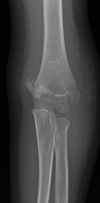

Fratura do platô tibial lateral - Schatzker tipo 2 (traço de fratura + depressão do plato lateral).